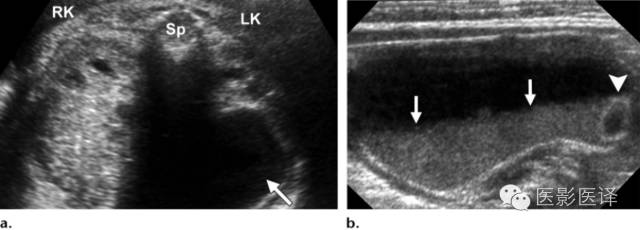

Nussbaum等最早将新生儿卵巢囊肿分为单纯性和复杂性。单纯性卵巢囊肿是圆的、无回声的、单房和薄壁的(图1)。它们更经常为单侧而非双侧、更经常为腹内而非盆腔内。单纯性囊肿内偶尔可见单个分隔(图2)。直径小于20mm的卵巢囊性结构被认为是成熟卵泡,为生理性而非病理性。直径大于20mm的囊肿则考虑为异常。“子囊”征描述的是囊内一个小的、圆形、无回声结构(图3)。既往报道认为这是卵巢囊肿的特征。【在一个23例囊性病变的研究中(包括新生儿、婴儿及儿童),11例发现子囊,占卵巢囊肿的82%(敏感度82%,特异度100%,阳性预测值100%),在其他囊性病变中未发现子囊,包括淋巴管瘤、肠重复畸形、肠囊肿、胎粪假性囊肿、阴道积液和脐尿管囊肿。】

图7 囊肿中的液液平面。(a)轴位胎儿超声图像显示在左肾(LK)前方一个孤立性囊性肿块(箭),脊柱(Sp)另一侧可以看到正常的右肾(RK),三周后的随访图像(未展示)显示团块中出现液液平面。(b)新生儿经腹长轴位图像显示一个薄壁囊性团块,有液液平面(箭),子囊(箭头)是卵巢囊肿的确诊征象。(c)新生儿矢状位T2WI显示一个出血性卵巢囊肿,有液液平面(箭)和低信号血液成分。